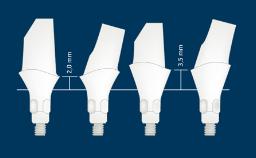

在制取种植体印模时,使用精确制作的取模柱来记录种植体的位置、排列和角度方向。无论是遵循传统(即替代体)还是数字化印模制取流程,印模都会记录这些与周围硬组织和软组织相关的信息。本模块将介绍传统印模技术和所涉及的所有参数。

- 定义传统种植体印模的取模柱和技术